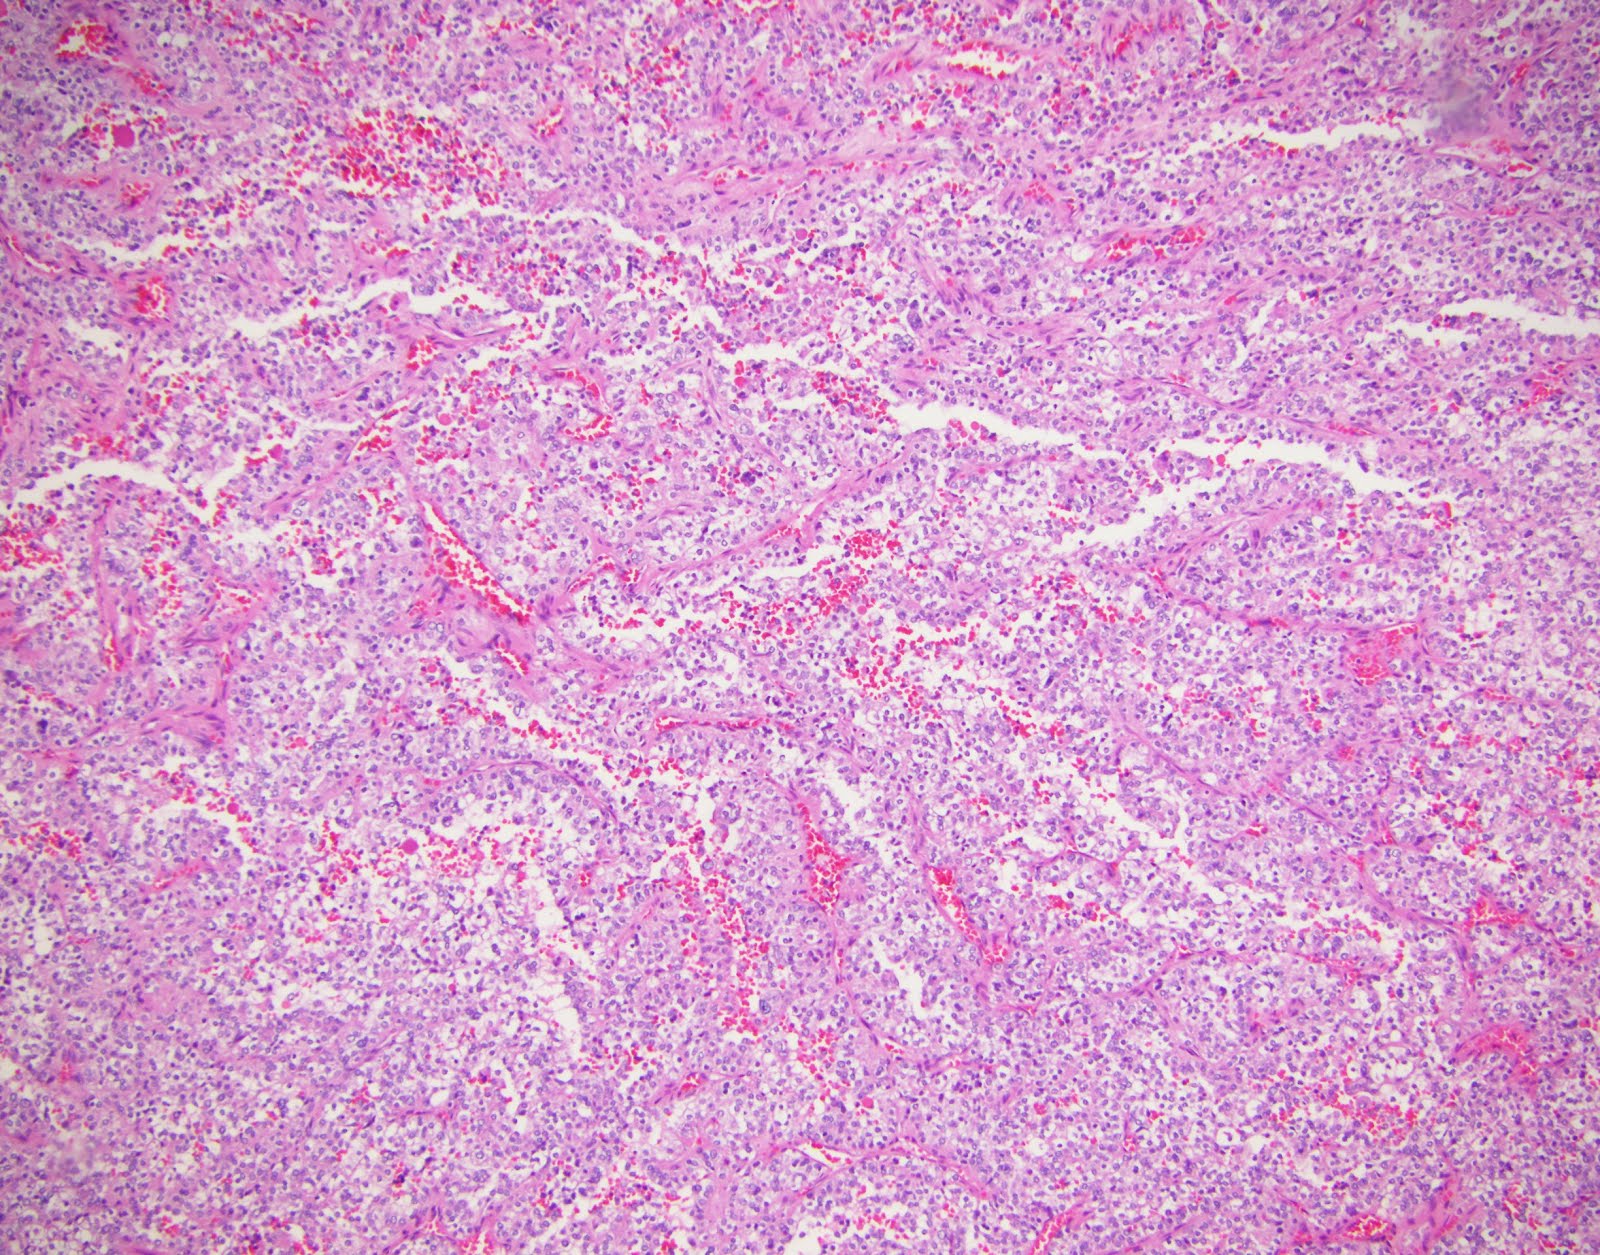

Mantle cell lymphoma

Mantle cell lymphoma 115 фотографий